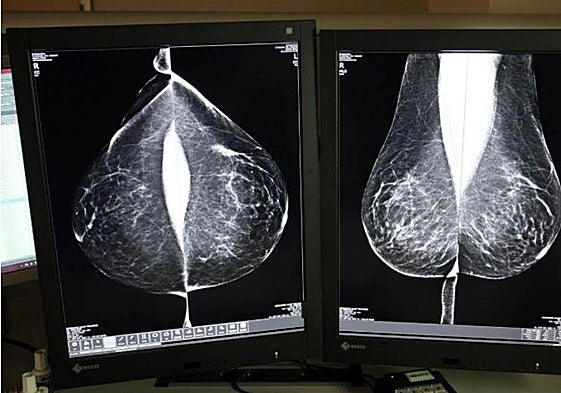

Castilla y León gestiona con la «mayor celeridad posible» las segundas pruebas en las mamografías dudosas

Fernández Carriedo explica que los médicos de Primaria informan a las pacientes cuando se descartan patologías